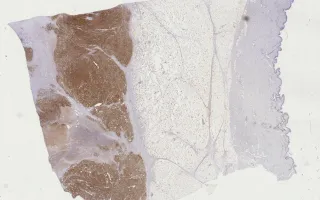

Breast, Epithelial-myoepithelial invasive carcinoma, S100 stain

Immunohistochemical staining shows that a majority of the cell population is positive for S100. Immunostaining for CK-7 and p63 shows scattered positivity.

This slide shows S100 stain. See related content for H&E, CK7, and p63 stains.